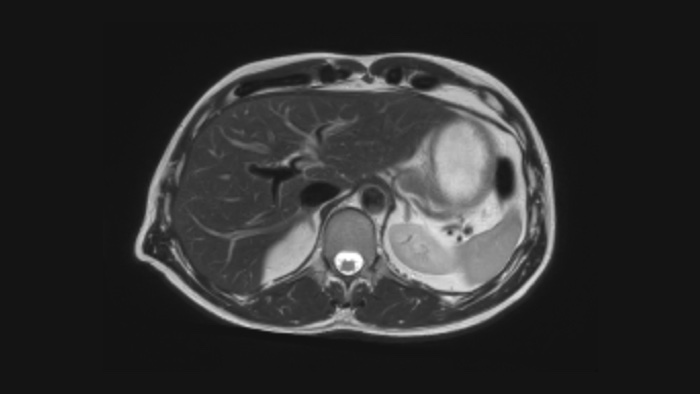

Affidabilità diagnostica Funzionalità di imaging ampliate in tutte le aree cliniche. Scopri i vantaggi di cui già si avvalgono i tuoi colleghi.

Questa soluzione innovativa offre numerosi vantaggi clinici, operativi e finanziari.